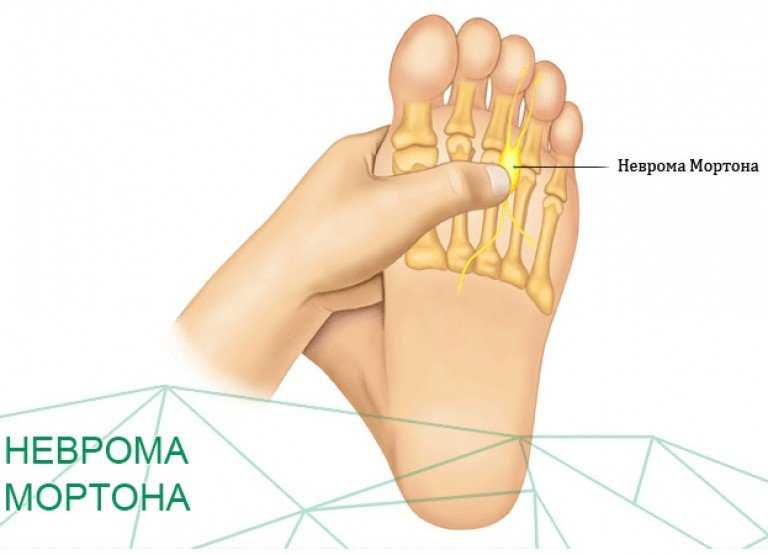

Разрастание нервной ткани, расположенной на подошве ноги, между 3-и и 4-м пальцами, называется невромой Мортона. Что это такое? Это фиброзное доброкачественное новообразование обычно поражает одну ногу, редко – обе сразу.

Заболевание проявляется в виде утолщения нерва на подошве, это сопровождается сильными болями, резко ограничивает человека в передвижениях. Когда у врачей появляется подозрение на развитие метатарзалгии Мортона, это говорит об опухолевом новообразовании нервной ткани, вызывающем сильные боли в плюсневых сочленениях.

Как лечить неврому Мортона, придется узнать на приеме у невропатолога. Отмечается, что чаще всего неврома поражает ноги молодых женщин. Невропатолог определяет патологию в межпальцевом пространстве у третьего пальца. Здесь нарастает уплотнение тканей с сильными болями.

По анатомии на этом участке стопы нерв делится на ветви, направляющиеся к боковым поверхностям пальцев, боль расходится именно в этих направлениях. По отзывам пациентов, столкнувшихся с невромой Мортона, они уже знают, что это такое и как лечить патологию, чтобы не довести болезнь до операции.